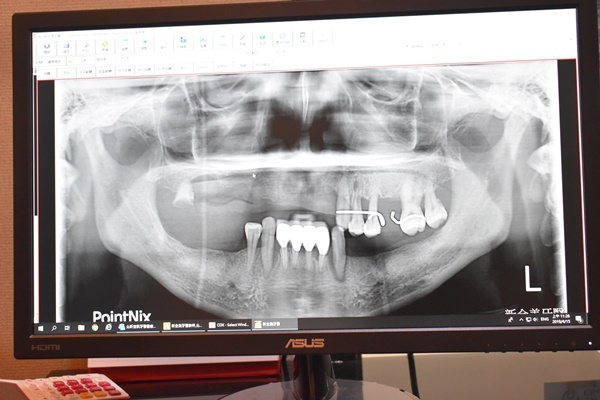

X光片清楚可以看到人工牙根(醫師說的植體)有些傾斜,牙根兩側白色骨頭凹陷明顯,果然之前做的植牙出現問題,經過朱醫師診治才確認出植體會搖晃發炎主因是牙齒骨頭密度不足關係所導致,據朱醫師說法非常保留客氣,僅用疑似的口吻帶入產生植牙失敗的原因,既然都遇到這樣的事情也只能請醫生幫忙接手處理…..